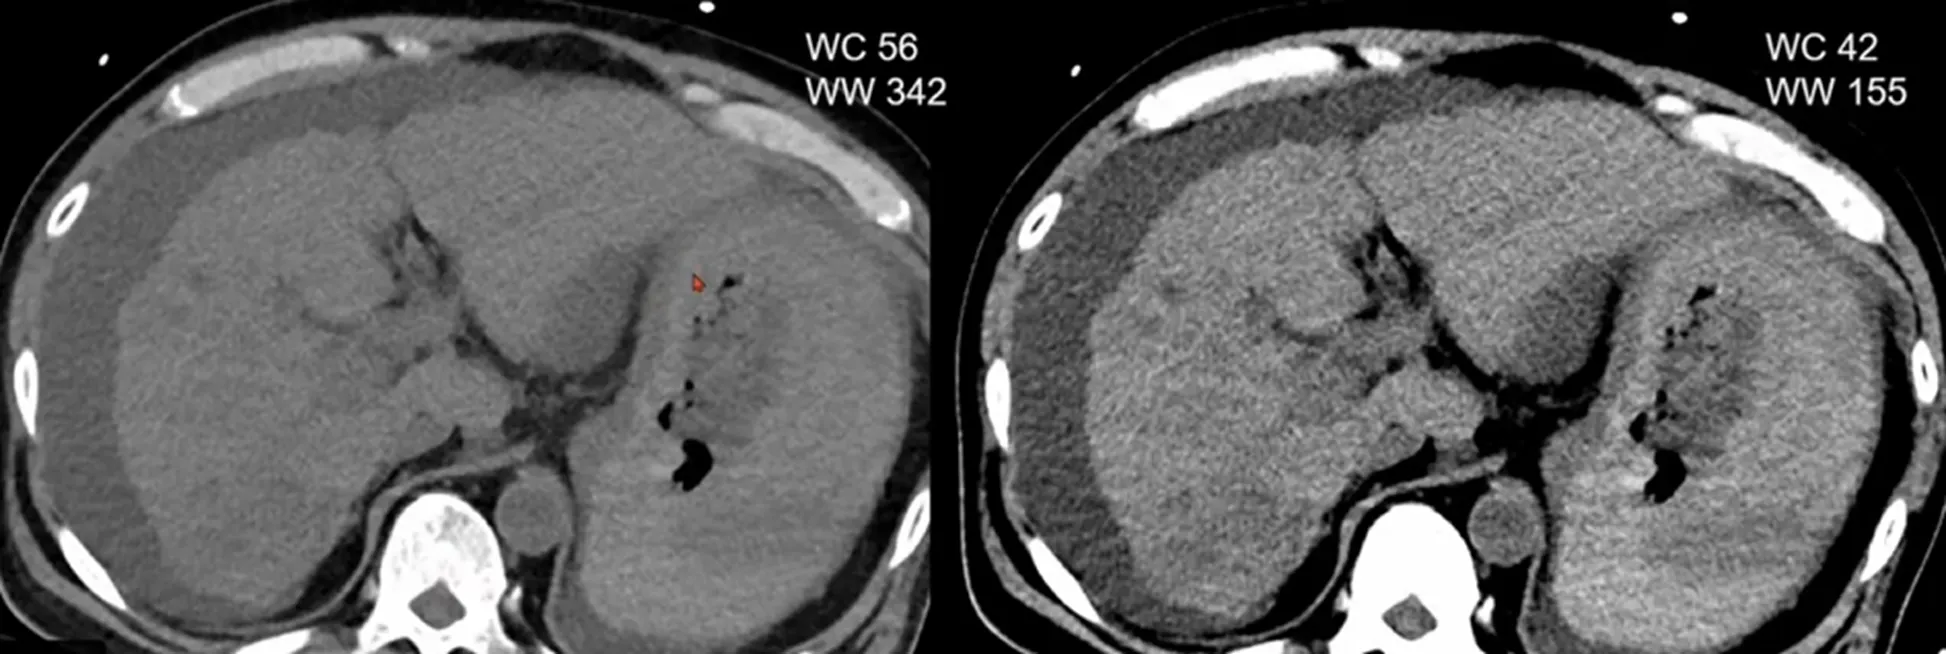

Tips for image setting: better to soft tissue contrast in plain CT

1. Window width, Window level Adjustment

Next day: repeated CT

알고 보니 hemobilia 환자

Hemorrhage 가 시간에 따라 attenuation 달라져서 .. Layered pattern

Hemorrhagic cholecystitis